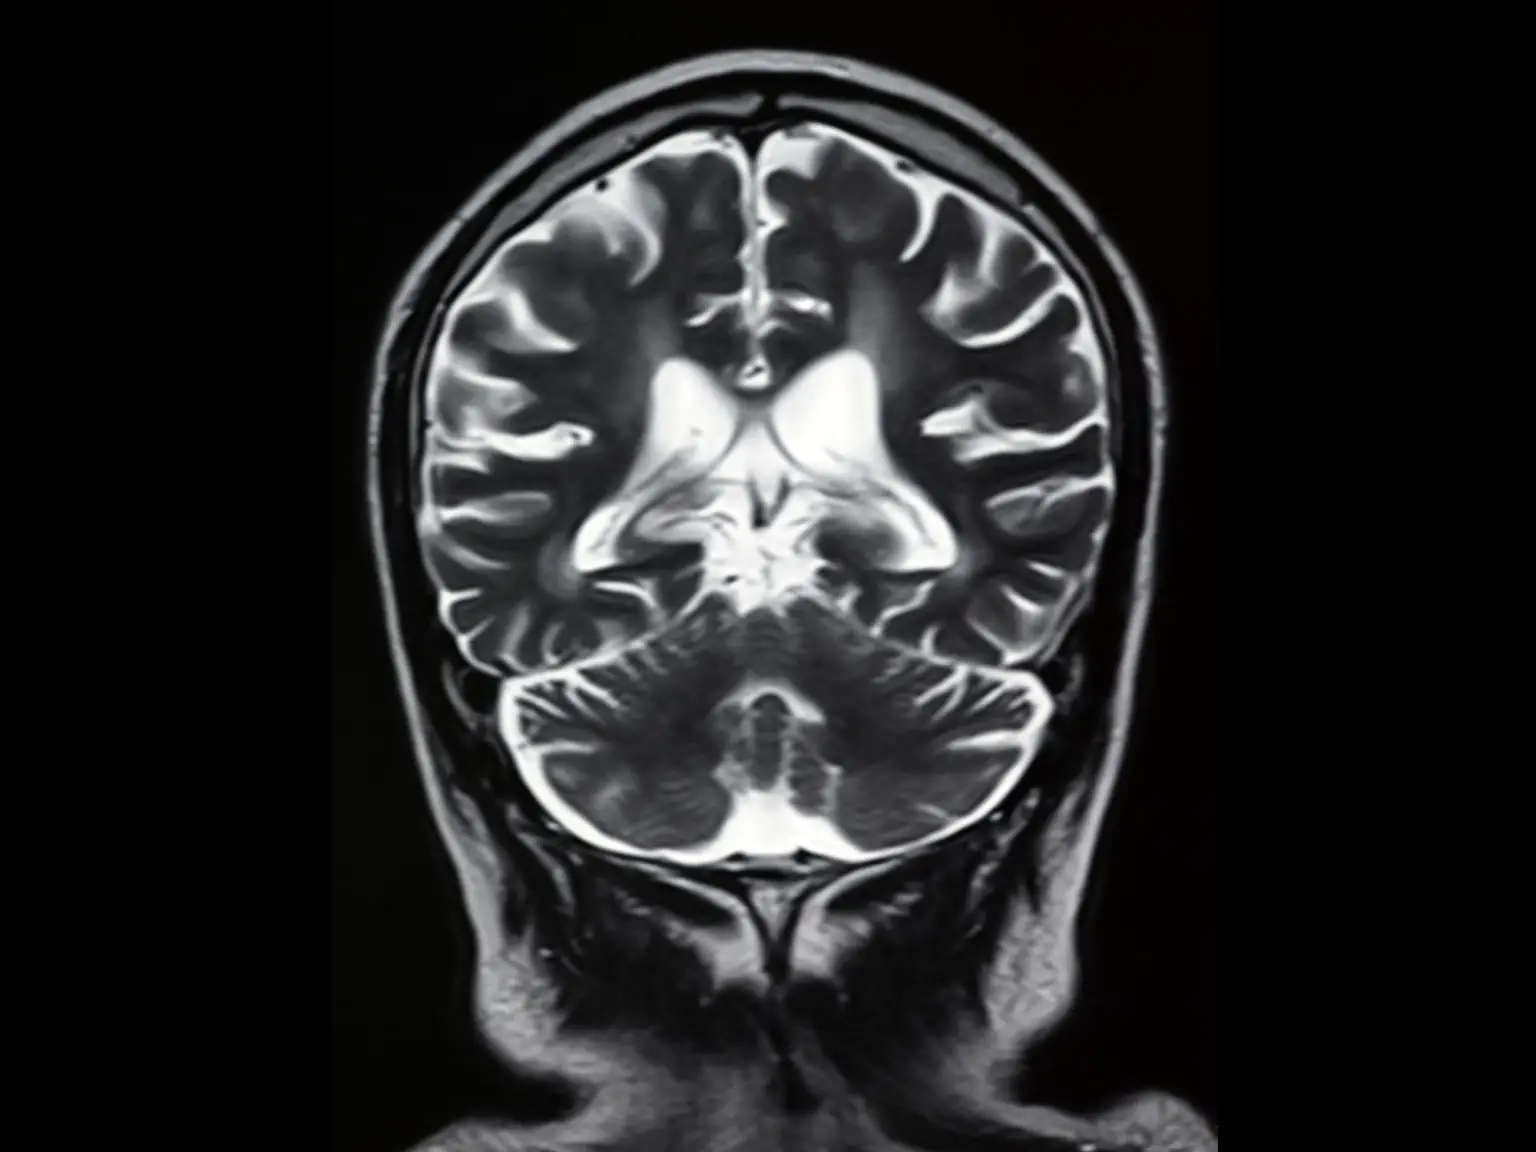

伦敦大学学院(UCL)研究人员领导的一项新研究发现,患有Long-COVID并失去嗅觉的人在大脑的某些区域显示出不同的活动模式。该研究使用核磁共振扫描来比较失去嗅觉的长COVID患者的大脑活动,那些在感染COVID后嗅觉恢复正常的人,以及那些从未对COVID-19检测呈阳性的人。

由UCL研究人员领导的一项最新研究发现,与那些已经恢复嗅觉或从未患过COVID-19的人相比,患有长期COVID并经历失嗅症(失去嗅觉)的人显示出不同的大脑活动模式。这项观察性研究使用了核磁共振成像扫描,发现患有长期COVID失嗅症的人的大脑活动减少,眶额皮层和前额皮层之间的交流受损。在那些在COVID后恢复嗅觉的人中,这种联系没有受到损害。研究结果表明,长期COVID无嗅症可能与大脑中阻止气味被正确处理的变化有关,但由于它在临床上是可逆转的,嗅觉训练可能有助于大脑恢复这种感觉。该研究还发现,长期COVID无嗅症患者的大脑可能通过增强与其他感官区域的连接来进行补偿。

发表在《电子临床医学》(eClinicalMedicine)杂志上的这项观察性研究发现,长期失去嗅觉的COVID患者的大脑活动减少,处理重要嗅觉信息的两个大脑部分之间的交流受损:眶额皮层和前额皮层。在COVID后恢复嗅觉的人中,这种联系没有受到损害。